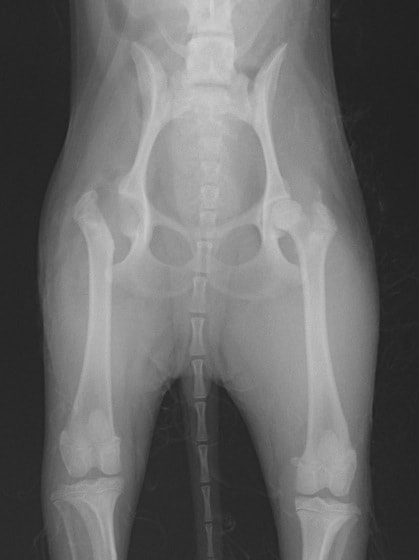

レッグペルテス病/無菌性大腿骨頭壊死症はトイ種やテリア種などの小型犬に好発し、5~8ヶ月齢の若齢期に多く発症します。大腿骨の先端(大腿骨頭)が、血液供給の障害により成長が阻害され、大腿骨頭の変形や壊死を起こす病気です。罹患動物は股関節の強い痛みのため、日常生活においては進行性の跛行(ケンケンをして歩く、足を地面に着かない等)の症状が認められます。肢を使わなくなるため筋肉量は減少し後肢は細くなります。

診断方法は主に触診と画像検査により行われます。触診では足を後方に伸ばし、疼痛の有無を調べます。レントゲン検査では、大腿骨頭や骨頸の骨密度の低下、大腿骨頭の辺縁部の変形、大腿骨頭や骨頸の亜脱臼等が認められることがあります。しかし発症初期では、レントゲン所見には異常が認められず、繰り返しのレントゲン撮影、CT検査を行う場合があります。

レッグぺルテス罹患症例の股関節のレントゲン写真